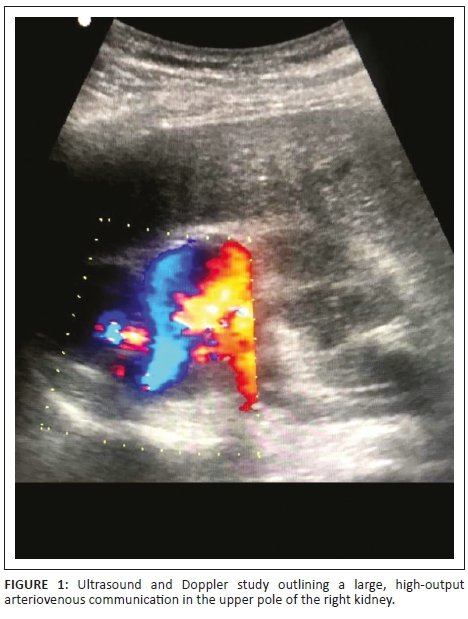

A 63-year-old male patient was referred with lower urinary tract symptoms, who never had haematuria but suffered from episodic right flank pains that he described as pressure like pains. There was no previous history of renal trauma, renal biopsy or renal surgery. Physical examination was unremarkable. Ultrasound study outlined a large, high-output AVM at the upper pole of right kidney (Figure 1). Computed tomography angiography demonstrated enlargement of the right main renal artery, its anterior branch and the upper pole segmental artery of the anterior branch. An arteriovenous fistula was noted between a branch of upper pole segmental artery and a single draining vein. No nidus was seen. Ectasia of the feeding arterial segment and aneurysmal dilatation of the draining vein was seen at the site of the AVM (Figure 2).

The two-dimensional mode ultrasound typically reveals a focal area of irregular connecting cystic lesions. Colour Doppler will demonstrate the presence of flow in these tortuous cystic areas, with a mosaic of colours indicating turbulent flow in these vascular malformations. Pulsed wave Doppler will reveal the presence of venous and arterial flow with high-flow velocity and turbulent diastolic flow. There is also spectral broadening present and pulsatile flow in the draining vein.9